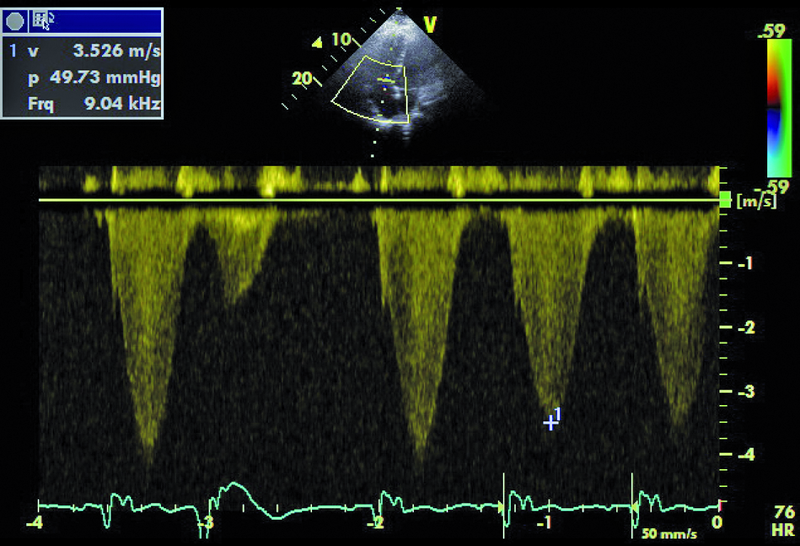

Mężczyzna, lat 30. Jakie patologie można rozpoznać na rycinach?

8. Nadciśnienie płucne (ryc. 6).

9. Komorowe zaburzenia rytmu (ryc. 1, 6).